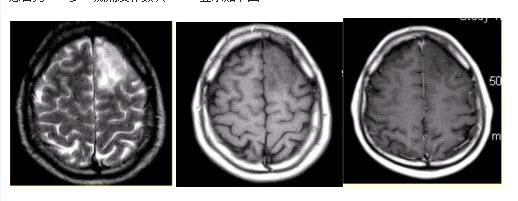

患者女,75岁,突发偏瘫、头痛、头晕10h。既往有高血脂、糖尿病史。MRI表现如下图。

患者女,75岁,突发偏瘫、头痛、头晕10h。既往有高血脂、糖尿病史。MRI表现如下图。

点击查看答案

C.矢状窦旁

E.灰白质交界区

患者女,75岁,突发偏瘫、头痛、头晕10h。既往有高血脂、糖尿病史。MRI表现如下图。

患者女,75岁,突发偏瘫、头痛、头晕10h。既往有高血脂、糖尿病史。MRI表现如下图。